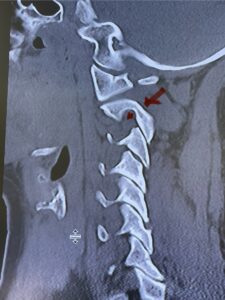

Fig. 6a: Sagittal cervical CT scan demonstrating an abnormally thin right C2 isthmus prohibiting safe placement of screw (red arrow). Notice the vertebral foramen eroding the isthmus bone structure (red dot).